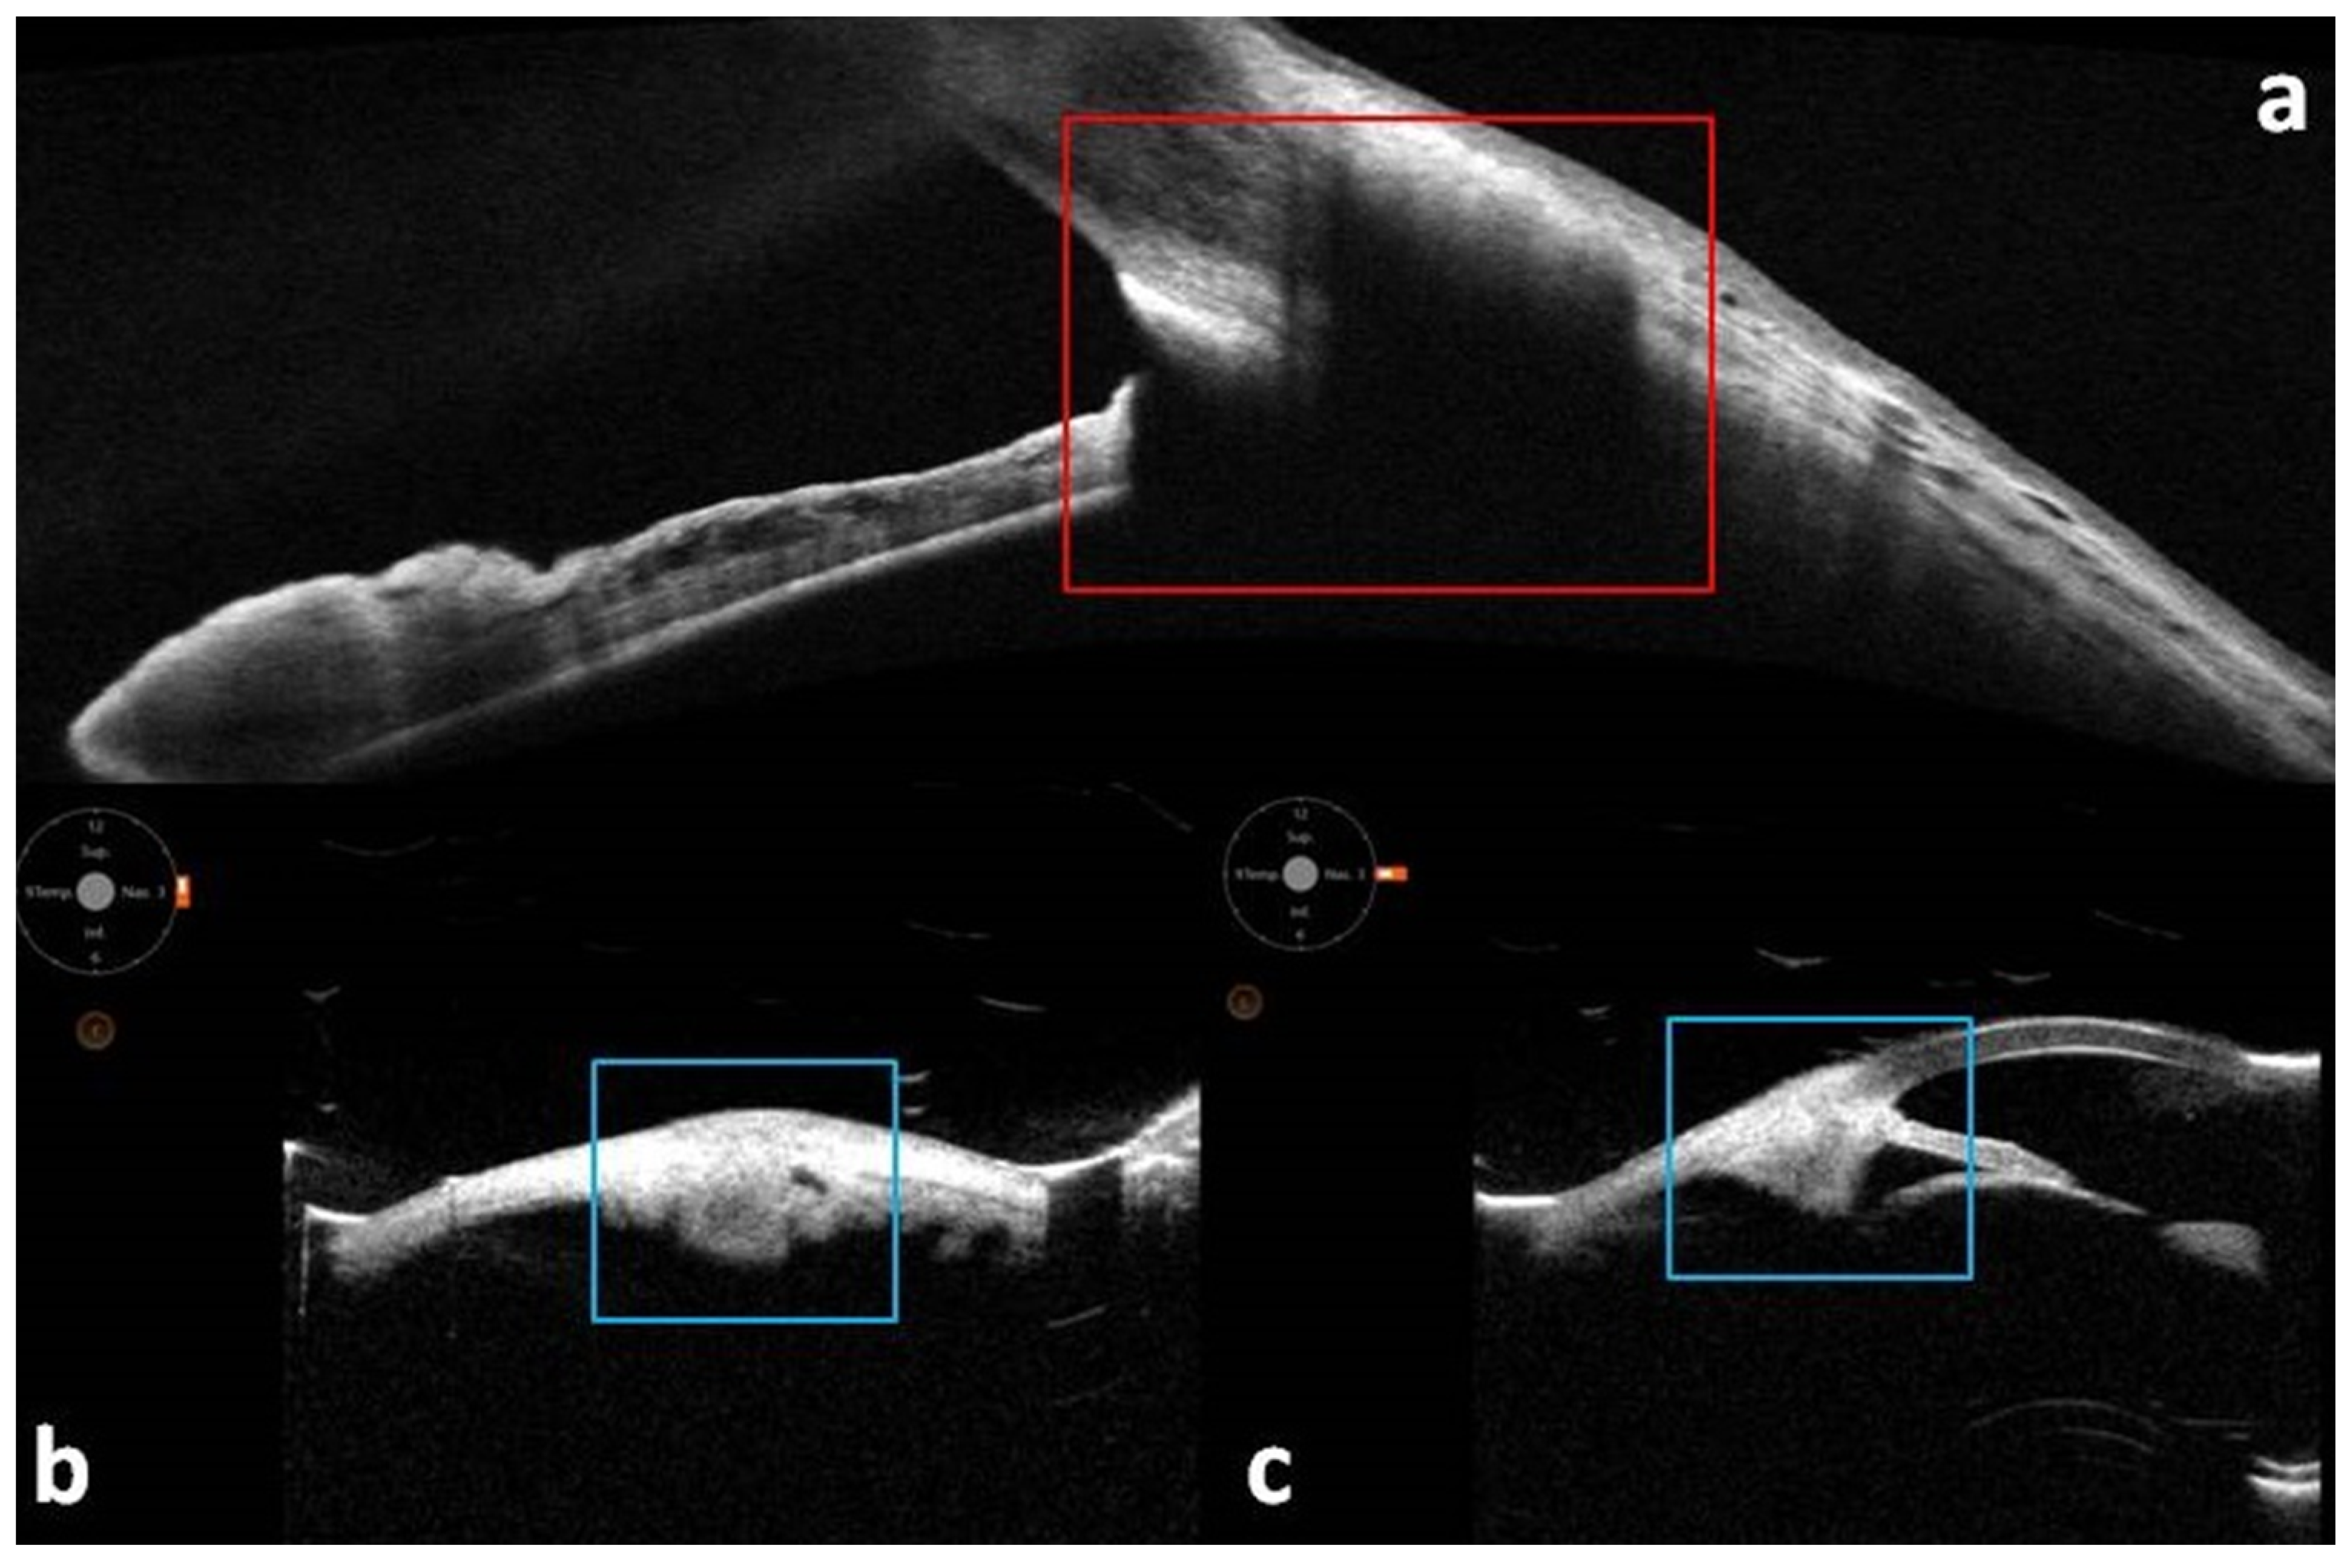

- Guner, M.K.; Ferenchak, K.; Olsen, T.W.; Dalvin, L.A. Optical coherence tomography findings in choroidal melanoma-associated subretinal fluid. Retina 2022, 42, 2159–2168. [Google Scholar] [CrossRef]

- Zhang, R.; Li, Y.; Dong, L.; Zhou, W.; Wei, W.; Liu, Y. Swept-source optical coherence tomography features of choroidal tumors and tumor mimics: A 5-year retrospective study. Photodiagnosis Photodyn. Ther. 2025, 53, 104571. [Google Scholar] [CrossRef]